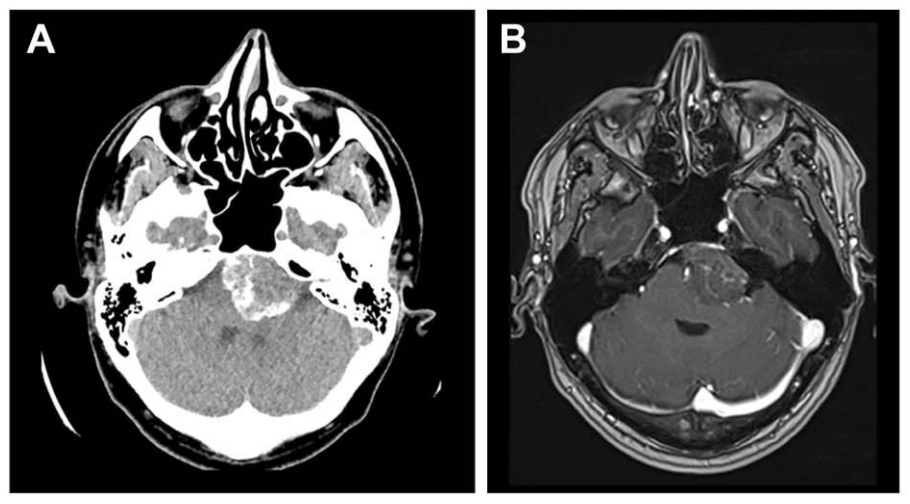

脑膜瘤是中枢神经系统肿瘤中,最具有特征性影像学表现的肿瘤。在X线和脑室造影的年代,检查结果仅起到提示作用。现在,影像学技术可以对脑膜瘤进行无创、准确地诊断,明确病灶与周围...

脑膜瘤是富血供肿瘤,血供可同时来自颅外和颅内循环系统。手术切除可能导致显着出血(平均200毫升2.2升)。栓塞术被提出作为一种有效的术前辅助治疗手段,旨在降低手术难度并减少并发症...

岩斜区位于颞骨岩部背面与枕骨斜坡部的岩斜裂汇合处,从岩骨尖至颈静脉孔。内侧至斜坡中线,外侧至第Ⅴ、Ⅶ和Ⅷ脑神经,上缘为鞍背,下缘为颈静脉孔水平;下方为枕骨大孔区。岩斜区脑...